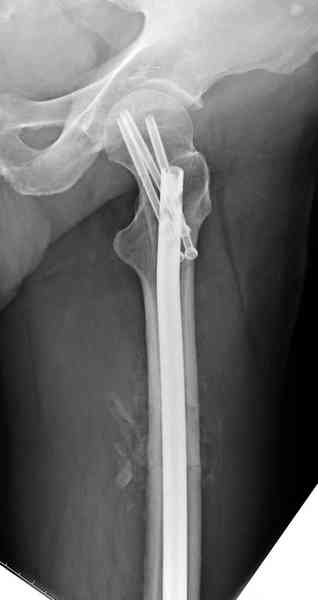

На второй день (7) обнаружен пропущенный перелом,

сделаны Компьютерная Томограмма

и проведены шурурпы через и спереди штифта без удаления.

Послеоперационные снимки